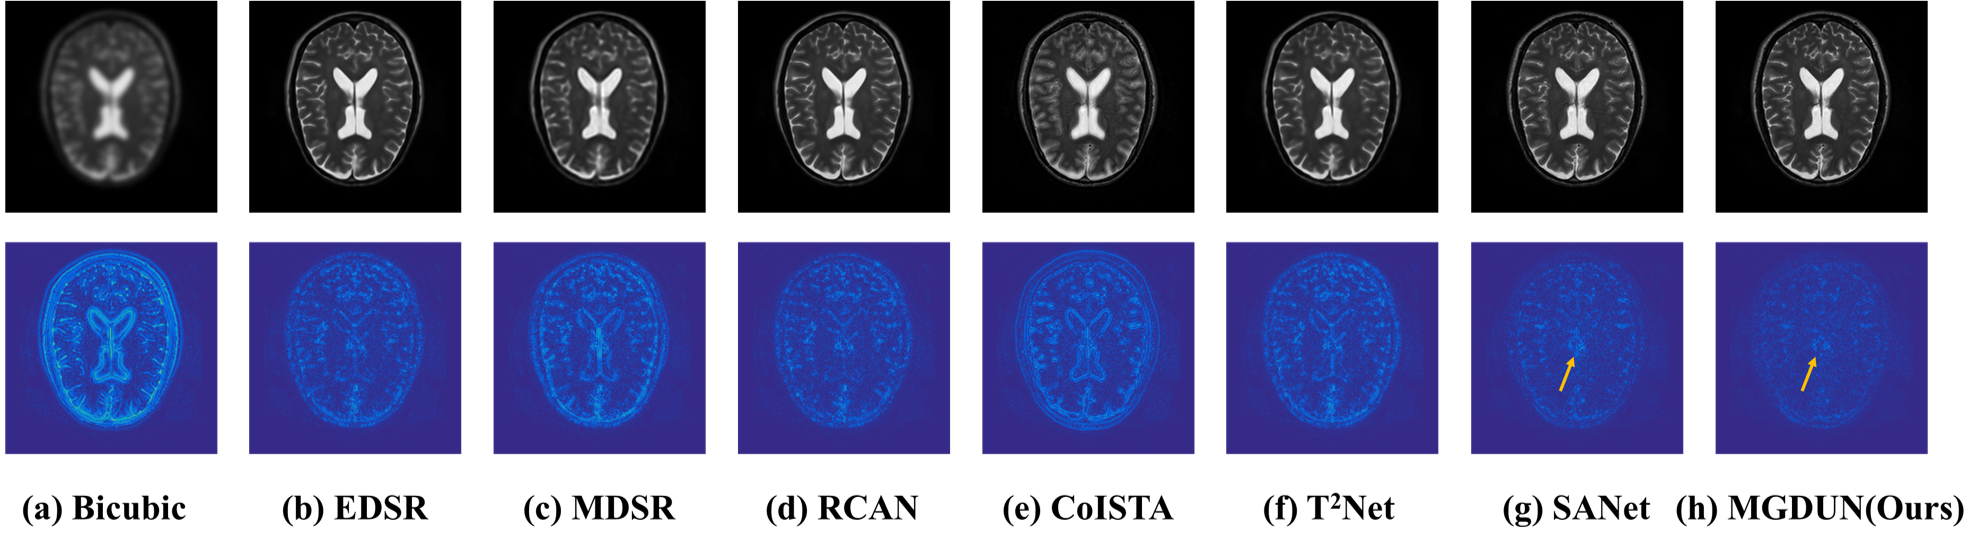

Refer to caption

Figure 3. Qualitative comparisons of all methods on IXI dataset. The first row visualizes the visual effects of different methods, and the last row visualizes the error map between the SR results and the ground truths.

4.3.2. Qualitative results

We provide qualitative comparison results on the IXI dataset as well as the BraTs dataset and their corresponding error maps in Fig. 3 and Fig. 4. The texture of error maps represents the restoration error, the smoother the texture, the better the reconstruction. As we can see, the input has significant aliasing artifacts and lacks anatomical details. It can be noted that our model recovers the image with fewer visible artifacts and reconstructs more details than other competing methods. The quality improvement achieved by MDCUN may be associated with the full usage of the feature maps from the former stages to refine the final results.